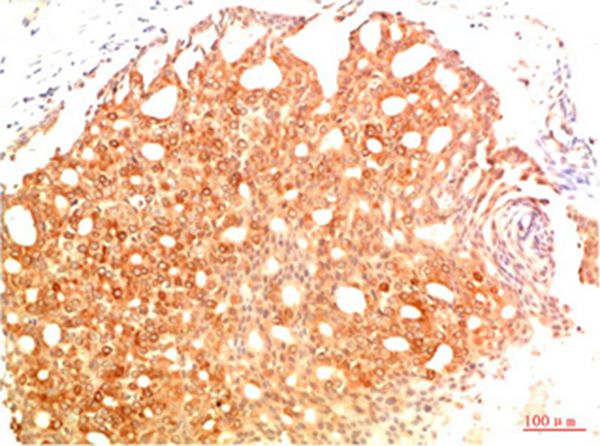

Immunohistochemical analysis of paraffin-embedded Human Colon Carcinoma Tissue using Acetyl P53(K382) Mouse mAb diluted at 1:200.

Immunohistochemical analysis of paraffin-embedded Human Breast Carcinoma Tissue using Acetyl P53(K382) Mouse mAb diluted at 1:200.